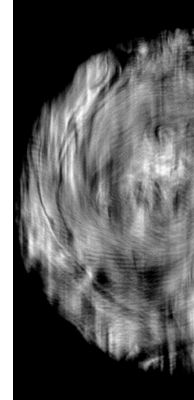

Reconstructed volume:

It was reconstructed a volume of 1978x1058x107 voxels. The DD stands for Distance-driven and DDb for Branchless-Distance-driven.